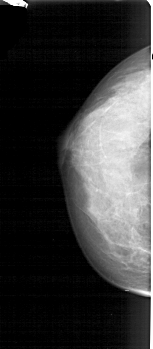

A_1606_1.LEFT_CC

LEFT_CC LINES 4531 PIXELS_PER_LINE 1981 BITS_PER_PIXEL 12 RESOLUTION 43.5 NON_OVERLAY

FILE: A_1606_1.RIGHT_CC.OVERLAY

TOTAL_ABNORMALITIES 1

ABNORMALITY 1

LESION_TYPE MASS SHAPE LOBULATED MARGINS OBSCURED

ASSESSMENT 4

SUBTLETY 2

PATHOLOGY BENIGN

TOTAL_OUTLINES 1

BOUNDARY